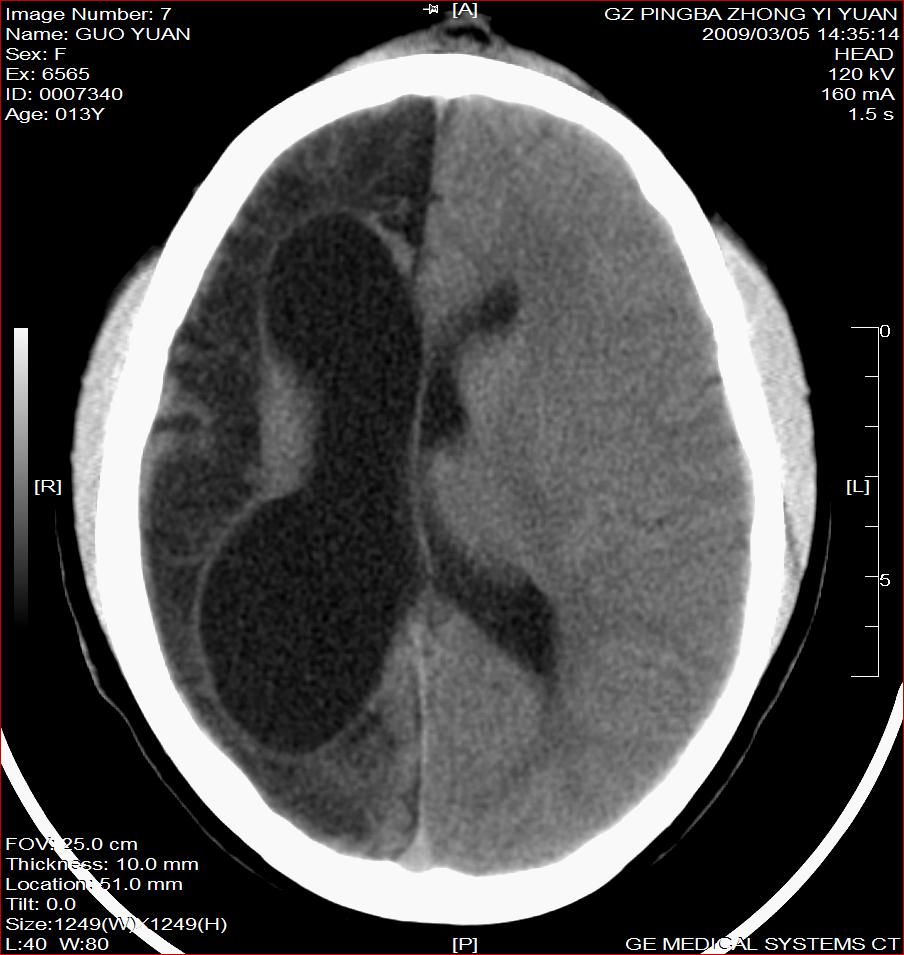

以下是引用杀毒软件在2009-3-6 17:32:00的发言:[br]右侧额颞顶部脑沟裂增宽,颞顶部楔形稍低密度影,侧脑室体部明显增宽,余脑实质内未见异常,中线结构居中。[br][br]考虑---右侧大脑半球发育不良并脑沟裂发育畸型可能性大

以下是引用随光逐影在2009-3-6 18:35:00的发言:[br]1)考虑右侧幕上半球发育不良并脑软化灶。2)双侧额部头皮软组织肿胀。